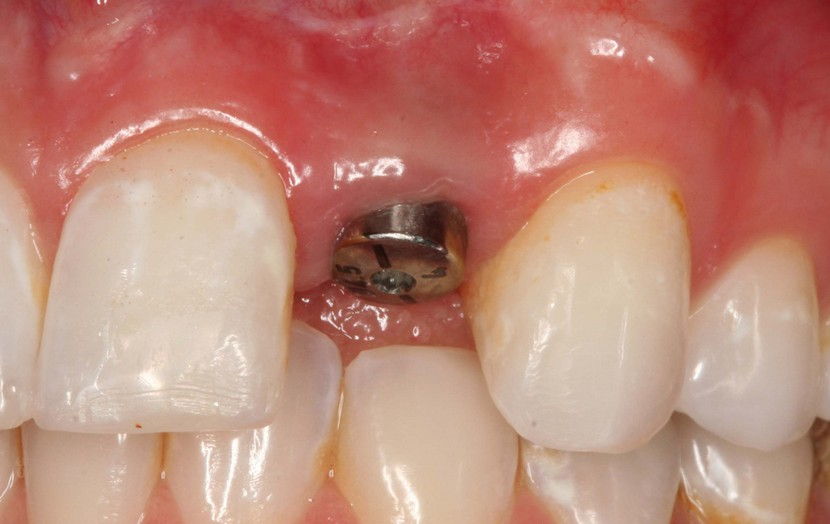

Dentalni implantat je najbolji način za nadomještanje izvađenog zuba. Implantat je vijak izrađen od titana koji se stavlja u kost malom kirurškom intervencijom. Cijeli postupak ugradnje traje oko pola sata i ukoliko se poštuju sva pravila nema većeg rizika i velikih bolova nakon samog zahvata.

Ugrađeni implantat zamjenjuje korijen ili korijene zubi koji nedostaju te postaje novi nosač navlake, mosta ili retencija za zamjenu ili lakše nošenje proteze.